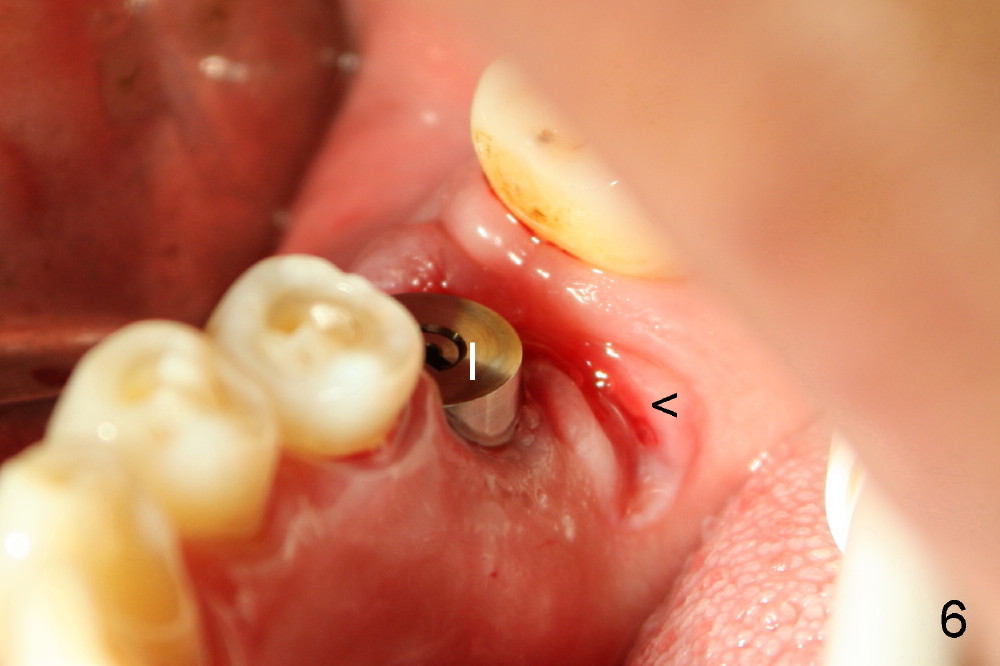

Drills are used to change osteotomy created by osteotomes more buccally. Taps are also applied. When 5x17 tapered implant (Fig.5 I) is inserted with torque >60 Ncm, the furcal gingiva (*) is further advanced distally to close DB socket (Fig.5 >) and DL one (Fig.6 <).